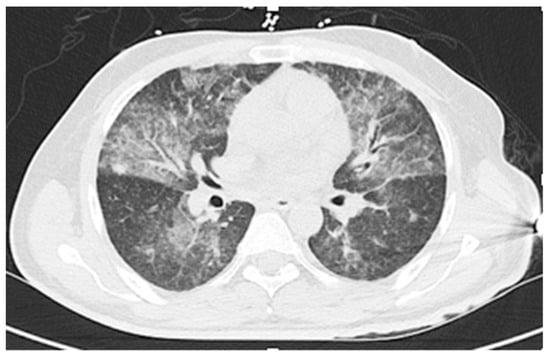

Hematologic results were: White cell count 5.3 K/µL with 36% neutrophils, 6% lymphocytes, 18% eosinophils, 20% bands, and 8% metamyelocytes; hemoglobin 9.7 g/dL; and platelets 138 K/µL. Serum chemistry values were: Sodium 120 mmol/L (RR 135-145 mmol/L) and bilirubin 1.6 mg/dL (0.2–1.2 mg/dL); creatinine, alanine aminotransferase, aspartate aminotransferase, and alkaline phosphatase levels were all within normal limits. A CT scan of the chest showed interval worsening as compared to three weeks prior, with extensive ground glass and patchy parenchymal opacities throughout the bilateral lungs, suggestive of multi-lobar Pneumocystis pneumonia (see Figure 5).

Figure 5. Case 2: CT of the chest showing extensive ground glass and patchy parenchymal opacities throughout the bilateral lungs; the differential diagnosis included opportunistic infections (pneumocytosis, cytomegalovirus), alveolar hemorrhage, and pulmonary edema.